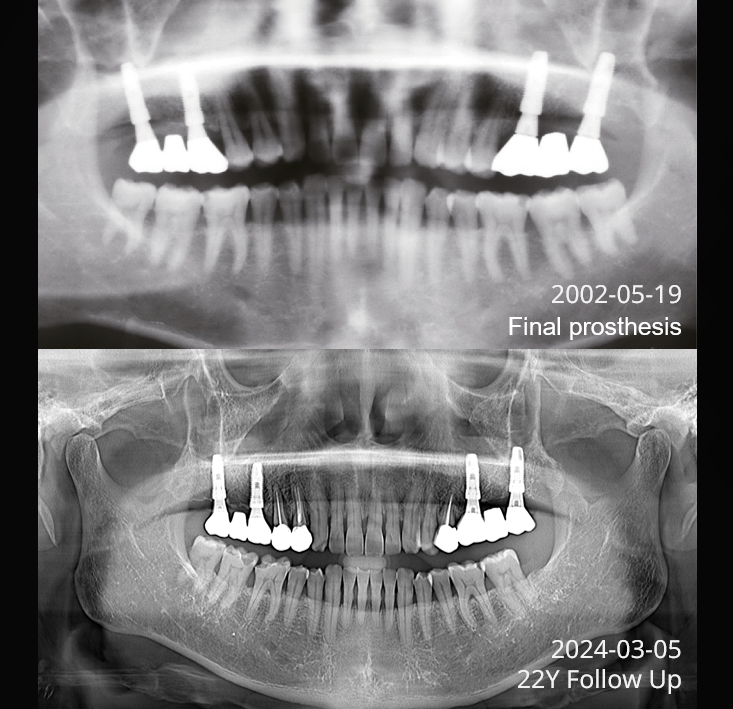

Proven Long-term ResultsBacked by over 20 years of clinical follow-up,

Implantium II proves its long-term stability and

reliability in diverse cases.